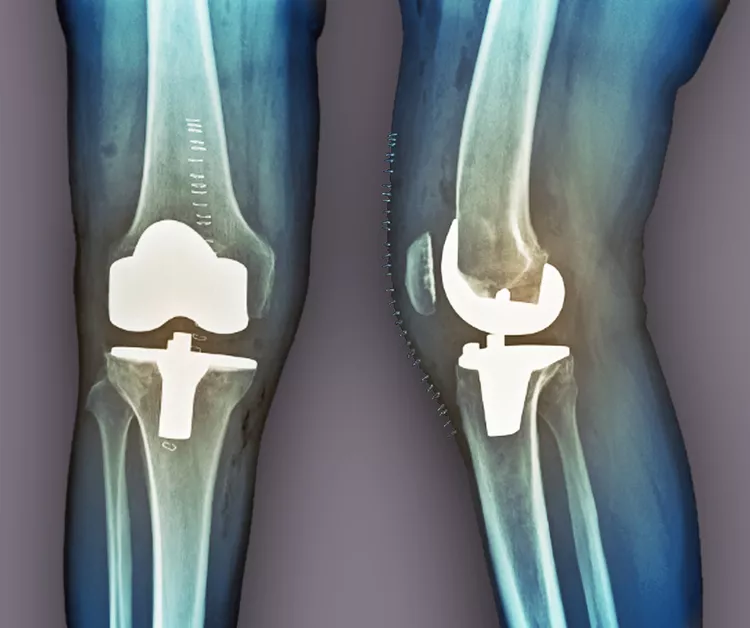

當其他療法失敗時,關節(jié)置換術是最后選擇。在這種手術中,醫(yī)生會切除膝蓋受損部位,并用金屬或塑料部件代替。如果這種方法不起作用,通過融合連接骨頭可能會緩解疼痛。缺點是,在這種手術后,其他關節(jié)最終會承受更大的壓力,以補償融合關節(jié)的運動損失。